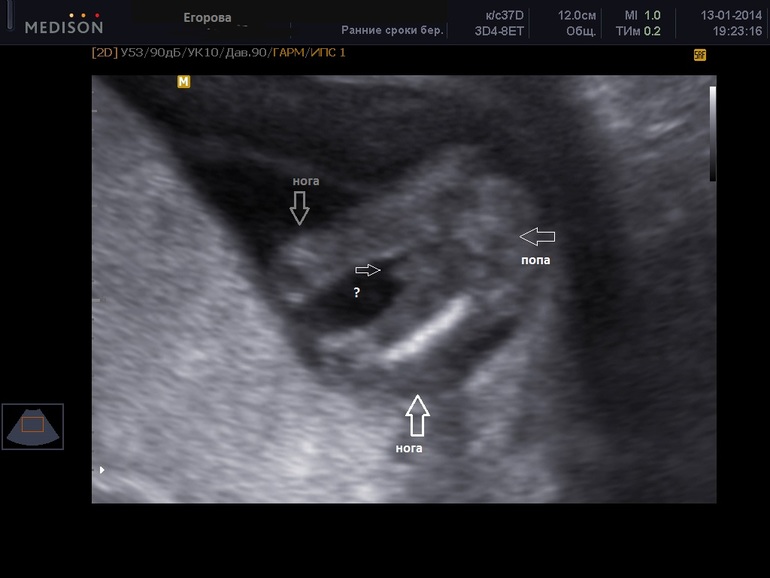

Девочки, фото узи 14 недель. Ваши предположения? Узистка сказала, что пол не понятен...

У девочек на этом сроке такой же половой бугорок как и у мальчика, только под другим углом. Так что по этому снимку невозможно определить пол. Придется вам потерпеть до следующего узи)))

Какая милая попка)))))Лесь, скажи мужу чтобы был готов ко всему) вдруг малышонок просто ручкой вам между ног махал?))))Не знаю, я вообще не верю в эти предположения и прогнозы) по опыту многих знакомым состоявшихся мам - вероятность того что узисты правильно пол предскажут такая же, как вероятность рождения М или Д - 50/50)

На 14 неделе и у девочек так между ног торчит, у нас так е было видно снизу, надо сбоку смотреть на этом сроке.